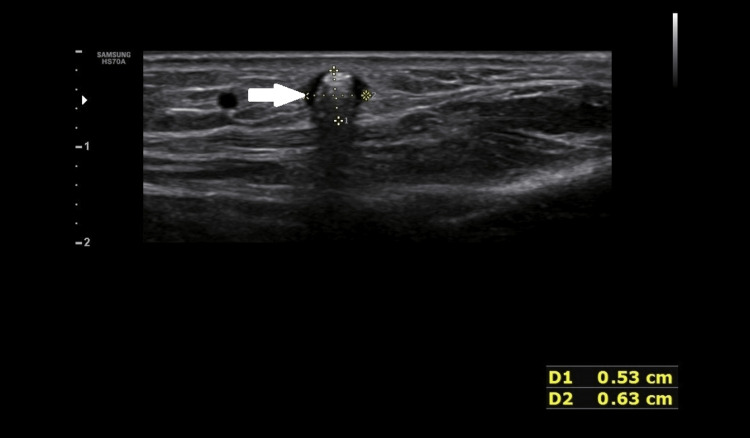

On B mode ultrasound, two round-shaped hyperechoic foci was seen, with the larger one measuring 06 x 05 mm, on a transverse scan in the subcutaneous plane in the region of swelling (Figure 2).

Figure 2. B mode ultrasonography image showing posterior acoustic shadowing (arrow).

These foci had posterior acoustic shadowing and showed twinkling artefacts on a colour flow ultrasound (Figure 3).

These echogenic foci were surrounded by hypoechoic hallow circumferentially and throughout their length.